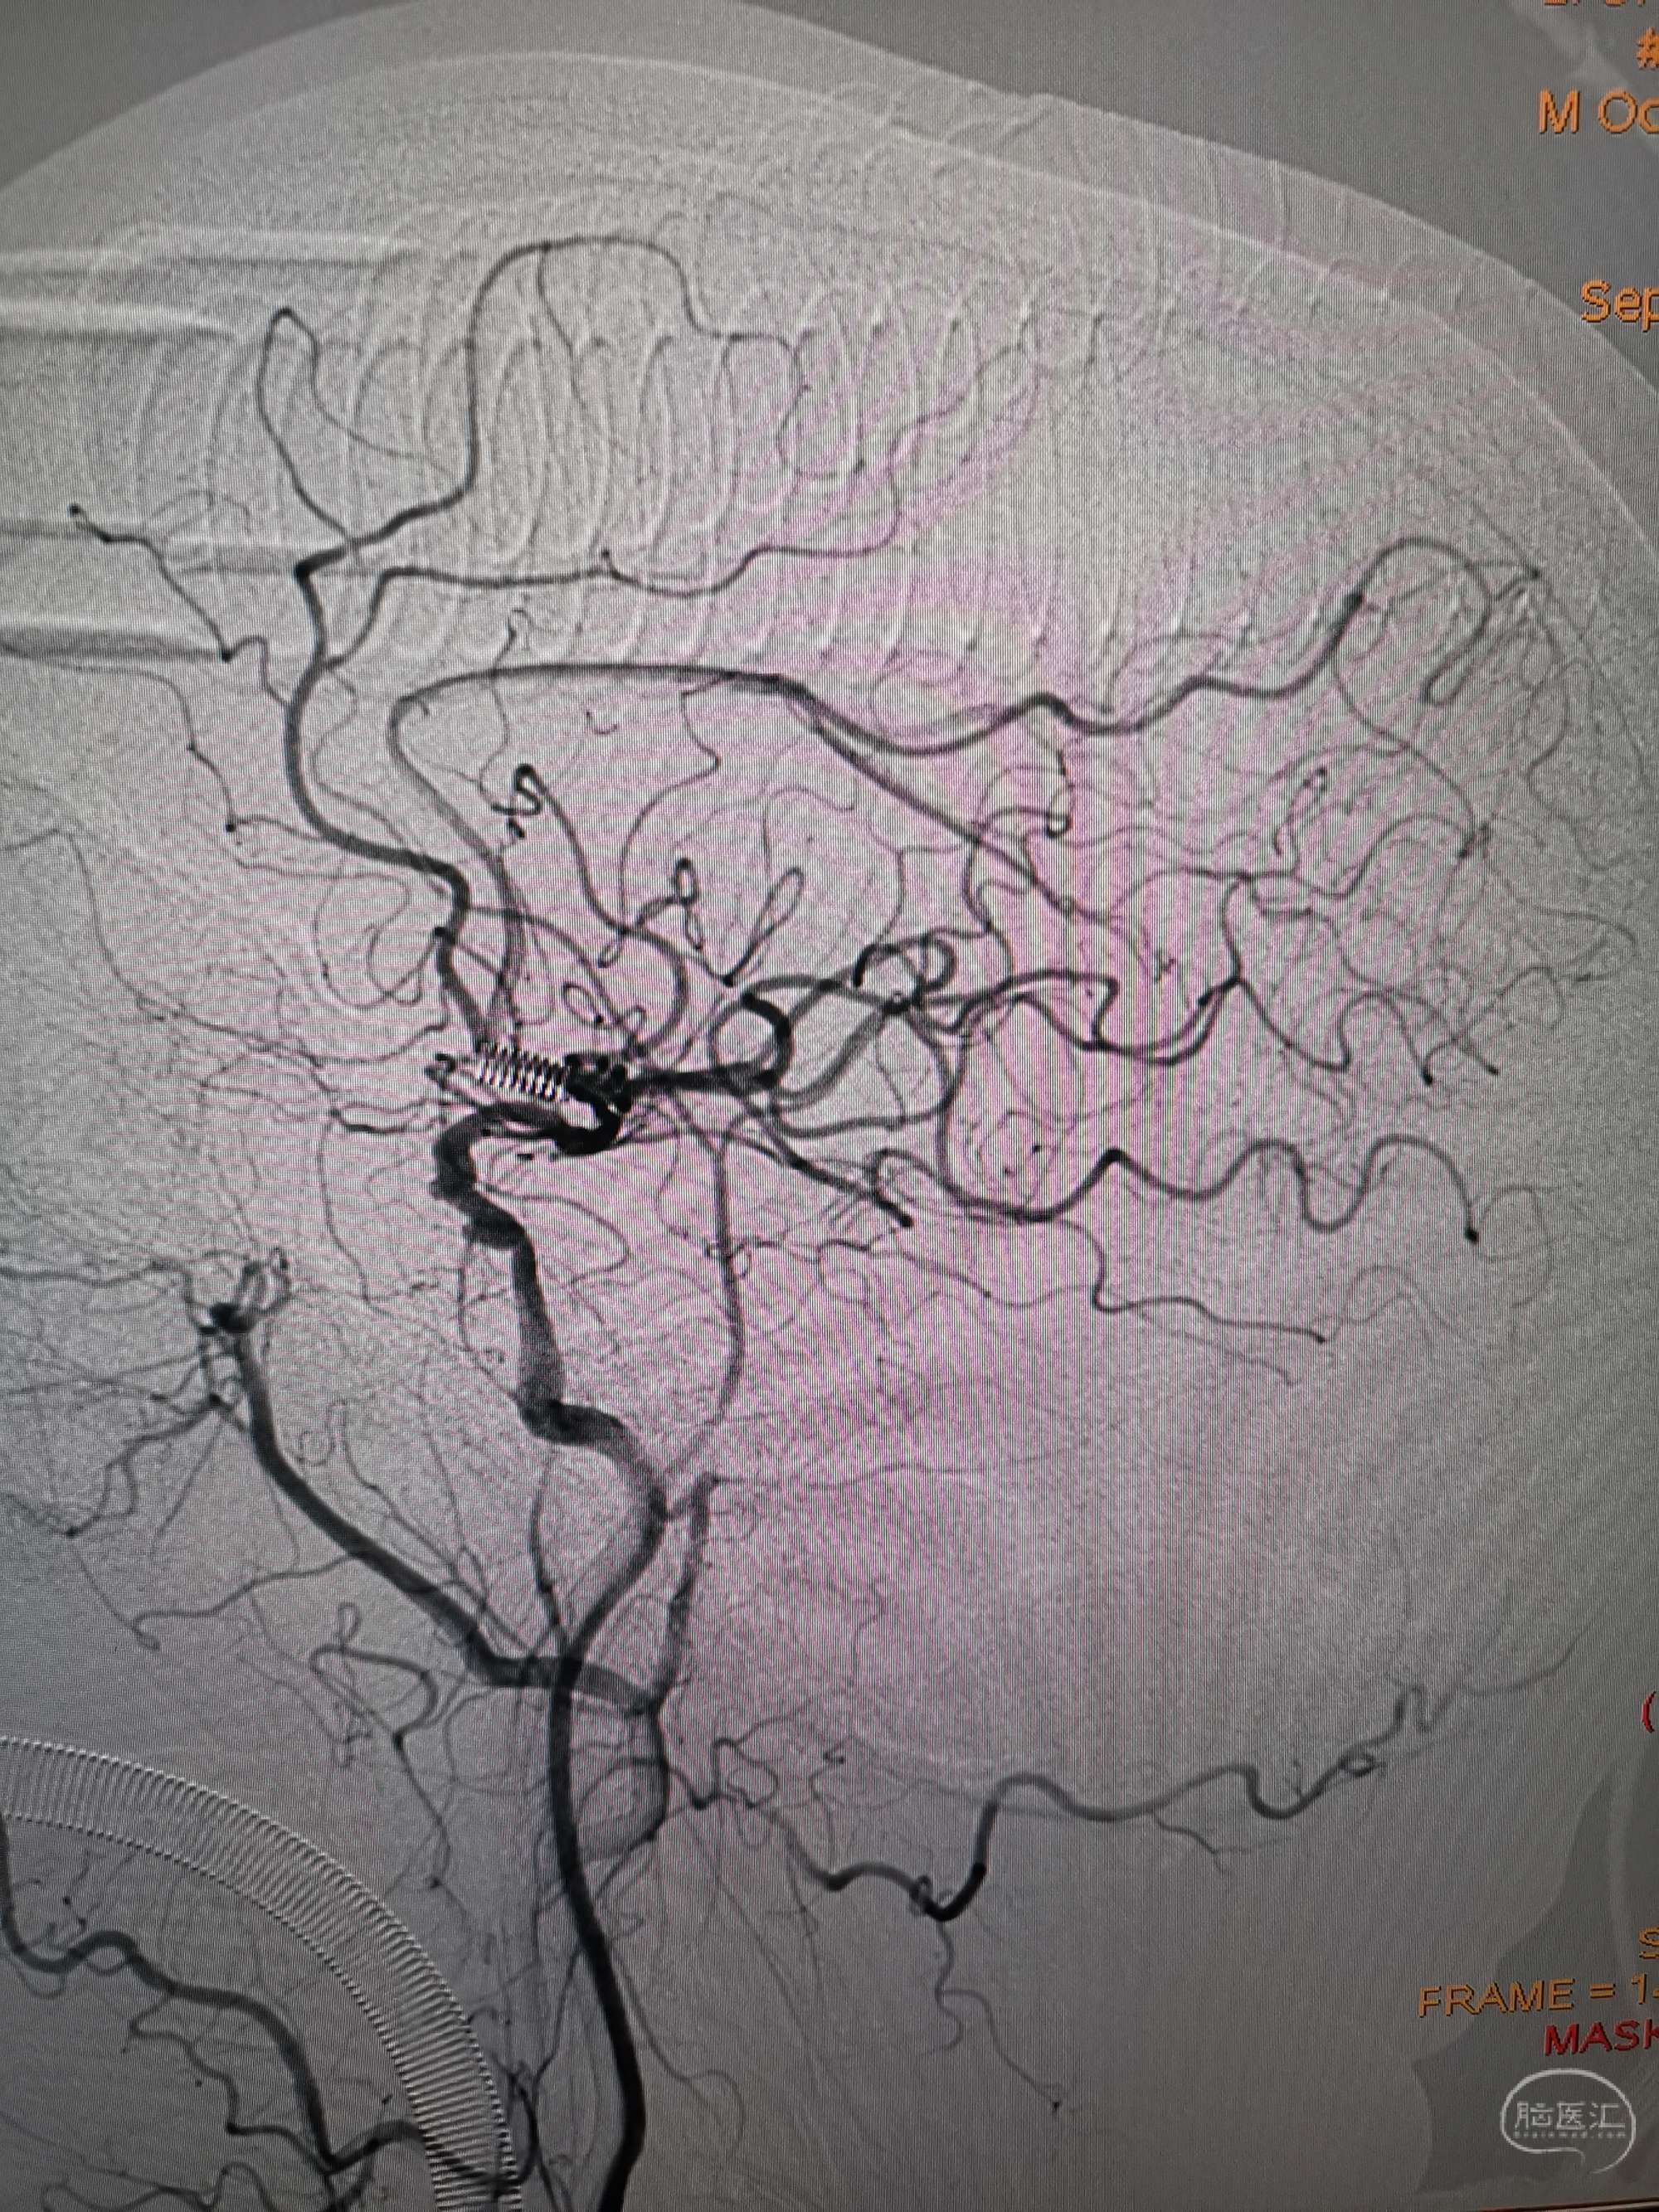

手术过程

在微导管支撑下先将微导丝和微导管穿过闭塞段,微导管超选造影证实位于基底动脉真腔后更换300cm外周交换导丝,撤出微导管后按从小到大,从远到近的原则行球囊扩张,本例手术选择了1.5✖️15、2.0✖️20、2.5✖️20球囊进行扩张,扩张满意后植入Enterprise支架,手术结束。

术后造影见左侧椎动脉闭塞段管腔恢复正常直径,远端血运良好。